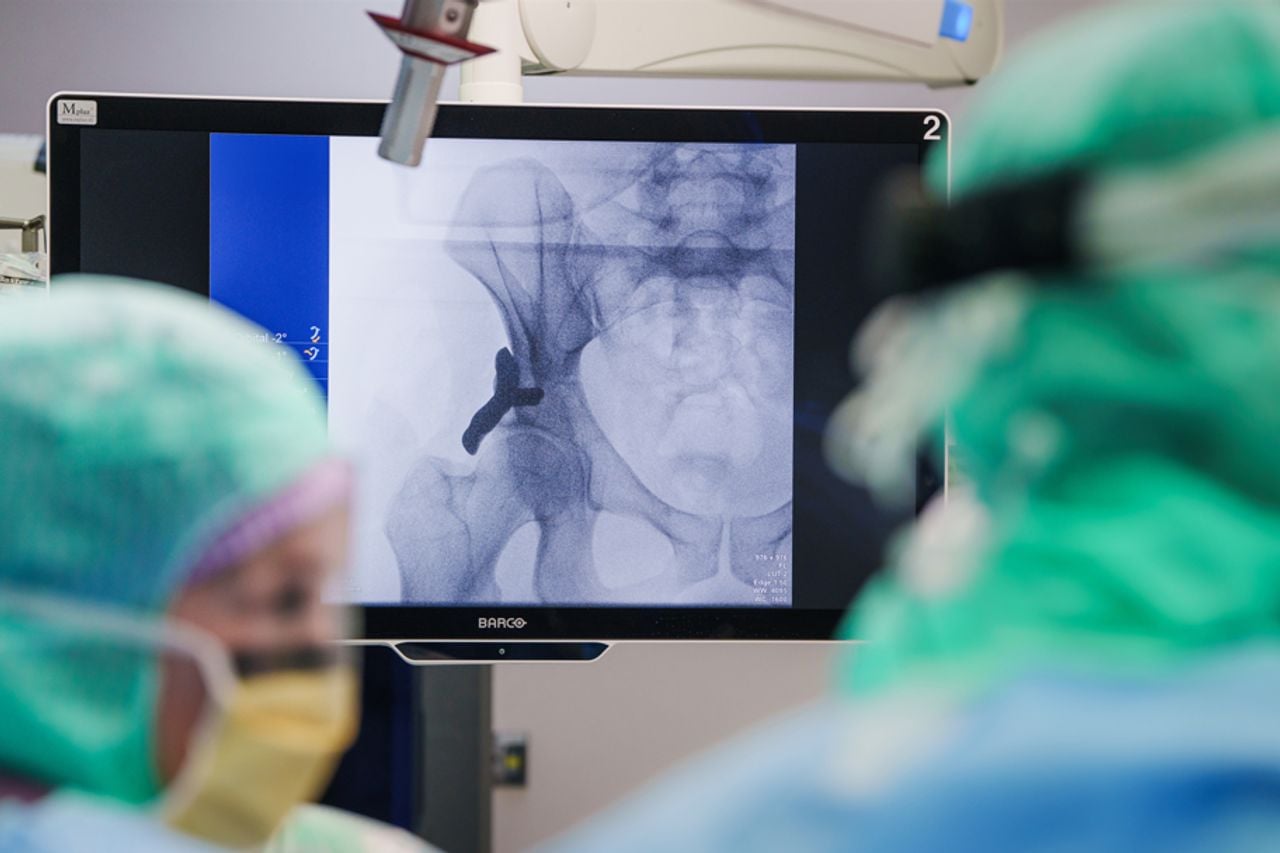

Een medische wereldprimeur in het Anna Ziekenhuis in Geldrop: daar is vrijdagochtend voor het eerst ter wereld een op maat gemaakt, 3D-geprint heupimplantaat bij een mens geplaatst. De operatie kan in de toekomst een zware en ingrijpende ingreep voorkomen bij mensen met heupdysplasie. Dat is een aandoening die vaak al op jonge leeftijd tot pijn en slijtage leidt.

Het nieuwe implantaat pakt het probleem op een andere manier aan dan de gebruikelijke operatie. Eerst wordt een CT-scan van de heup gemaakt, waarna op basis daarvan een persoonlijk implantaat wordt ontworpen en 3D-geprint. Het implantaat wordt als een opzetstuk op de bestaande heupkom geplaatst, zodat de heupkop beter wordt ondersteund.

Volgens Van Roosmalen is het een wereldprimeur omdat deze techniek nog nooit bij mensen is toegepast. “Het is een gepersonaliseerde aanvulling op het eigen bot, ontworpen om precies die plekken te ondersteunen waar de heup door dysplasie onvoldoende dekking heeft,” legt ze uit.